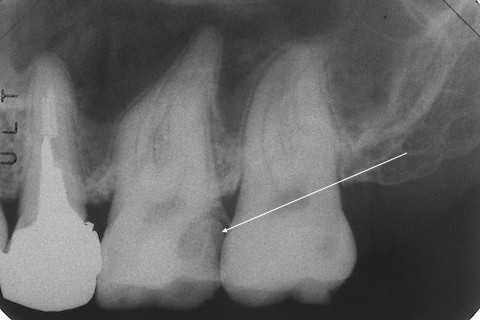

今日の充填治療3.60(ドイツのCR充填)

20代女性、左下56、辺縁漏洩による温冷水痛ドイツの歯医者さんでしてもらったCR充填が上手くいかなかったようで、沁みる。5年程経過して、ちょっと記憶が曖昧になってきたのだが、他にもこういう症例は見たことがあるような気がする。欧米のCRのボンディング材は湿式とか言って、接着面が水分で濡れていないといけないとかいうのがある。今もあるのかどうだか知らないが、さすがに水をエアブローで完全に乾燥させない方が良いというボンディング材がいいとは思えなかったので、僕は一度だけ試用しただけで採用しなかった。濡れが多すぎると漏洩の原因になって沁みたり、2次カリエスの原因になると思う。この症例のボンディング材がそれかどうだかは知らないが、アメリカの歯医者さんでしたCRも沁みるのでどうにかして欲しいという症例にも出会ったことがある。レントゲン写真でも隣接面下のカリエスがあるように見えるが、問題ないと言われた?かなり記憶が不鮮明になってきているので、ご本人が見ていらっしゃったら訂正して欲しい。見た目もちょっと、どーかなー?と言った感じだ。とりあえずCRは除去して接着マージンを出して再CR充填した。2回法でしている。1回目は気泡等が入らないように目視下で過不足の無いように、マージンからの漏洩が無いように気を使う。2回目はストリップスを使っても良い。では時系列でどうぞ

40代女性、右上6、温冷痛+、時々痛い他院(よそ)で神経を取るといわれたので当院(うち)に来られた。露髄(神経が出ている)してて痛みがあれば神経は治る見込みがないので、罰髄>被せとなるのが一般の治療方針だが、そうでもない。というかほとんどそんなことはしなくても良い。矢印部分が神経が露髄してる部分だが、α-TCPセメントで直接覆髄してCRで再建すれば問題ない。では時系列でどうぞ

21歳女性、右上2、隣接面カリエス前回のつづきhttps://plaza.rakuten.co.jp/mabo400dc/diary/202108290000/前歯部の隣接面カリエスがなぜできるかというと、唾液量が少なく、その緩衝能(酸を中和する能力)が低い、あまり喋ったり食べたりしない(唾液が回らない)、逆に飲食の頻度が高い(酸産生菌による酸の代謝)、その部位の酸素濃度が低い(酸素濃度差による腐食電池の形成)、例えば口唇をきつく閉じているなど。この子の場合、虫歯菌は少ないが、唾液が少なくの緩衝能が低く口腔内がいつも酸性に保たれやすいように思える。また口唇をきつく閉じているそうなので、前歯の酸素濃度が低くなりやすく酸素濃度差腐食は起こりやすいと思われる。これが4年前の画像。この時から隣接面カリエスの萌芽があった。これは4年後の画像レントゲン写真では象牙質まで進行してしまっている。左上1にもC2があるが今回は予防治療することにして介入していない。右上2は介入してCR充填することにしたが、ダイアモンドバーの先端の直径が1mmなので、これ以下の切削量に抑えることはできない。さらに隣の歯を切削バーで傷つけないようにするのが難しい。では時系列でどうぞ